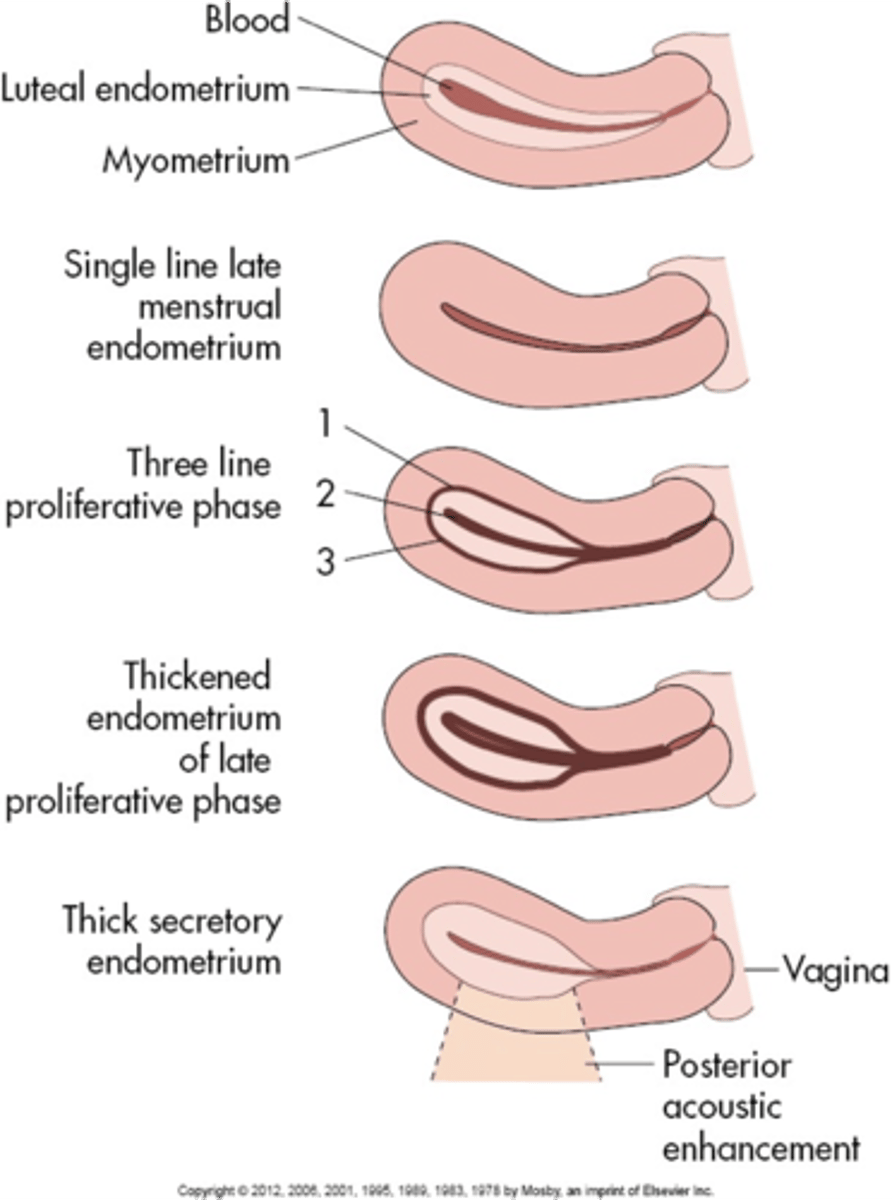

During the menstrual phase, the endometrium appears ___ and ___

thin; bright

During the early proliferative phase, the endometrium appears ___ and measures ___

bright; 4-8 mm

During the late proliferative phase, the ___ is visible and endometrium thickens to ___

3 line sign; 6-10 mm

During the secretory phase, the endometrium appears ___ and ___ and measures ___

thick; echogenic; 7-14 mm